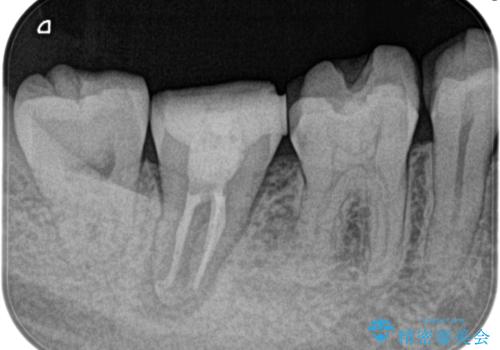

湾曲根管。精密根管治療

- 主治医から補綴前に根管治療を紹介いただいた患者様です。

検査の結果、右上第一大臼歯の診断を、歯髄壊死とし抜髄を行っております。

右上第二大臼歯は主治医にて治療の検討をしています。

湾曲根管に対してエラーなく処置を行えております。